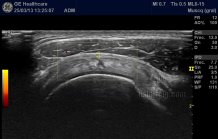

Participación española en un curso europeo sobre Ecografía Músculo-esquelética (03/10/2014)El doctor José Miguel Senabre, reumatólogo del Departamento deSalud de la Marina Baixa, ha participado recientemente en el 21 Curso de la Sociedad Europea de Reumatología (EULAR) sobre Ecografía Músculo-esquelética, celebrado en París.

El curso, en el que han participado más de 180 profesionales de todo el mundo, 7 de ellos españoles, ha contado con los principales expertos internacionales en este campo y tiene como objetivo continuar con la formación en el uso de esta técnica, que ha crecido de forma exponencial en las últimas décadas.

Además, como explica el doctor Senabre, “esta técnica ha demostrado gran utilidad en la evaluación de pacientes con artritis reumatoide, artritis de la temporal, gota o patologías de partes blandas como la tendinitis o el síndrome de túnel carpiano, entre otras enfermedades”.

En este sentido, su utilidad depende en gran medida de la habilidad y el entrenamiento del profesional sanitario que la realiza, por lo que es importante que se realicen cursos de formación continuada en este campo.

Así, durante 2013, la sección de Reumatología del Departamento de Salud realizó 979 ecografías, como prueba diagnóstica.